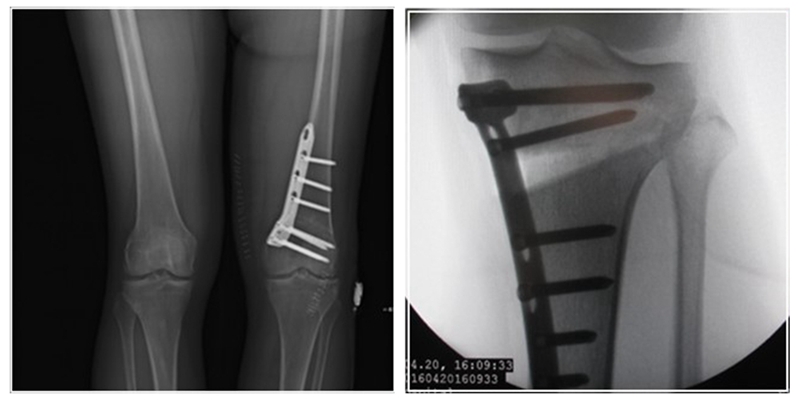

术后影像

经典病例